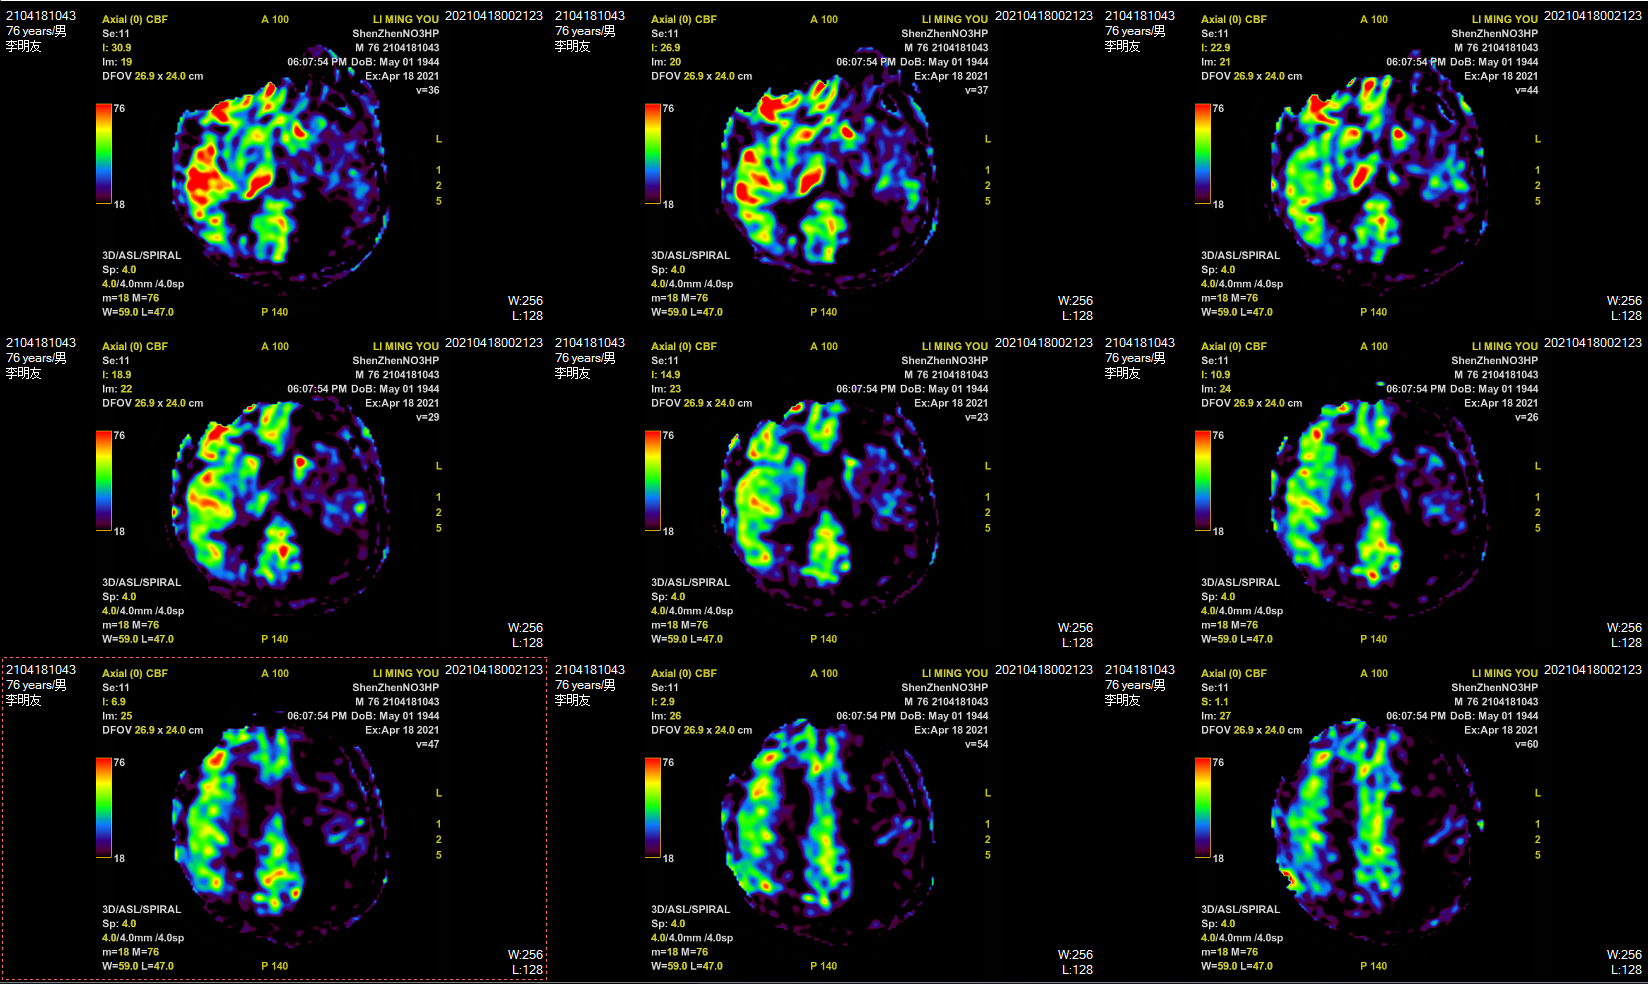

PWI示左侧大脑半球低灌注